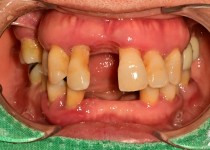

만 52세 전악 상악, 하악 전체 임플란트…

만 56세 상 하악 임플란트 증례

만 82세 하악 풀아치, 상악 임플란트(일…